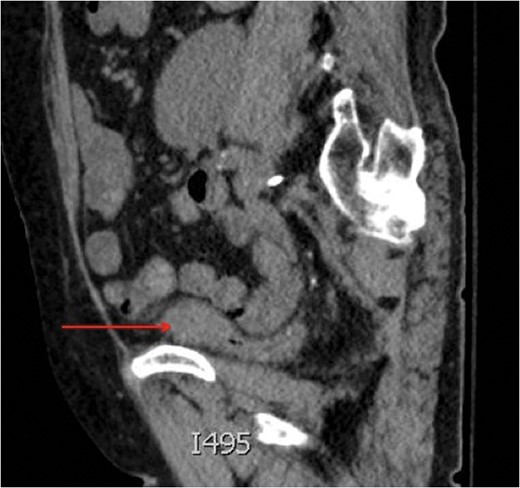

Saggital view of a mass at the dome of the decompressed bladder.